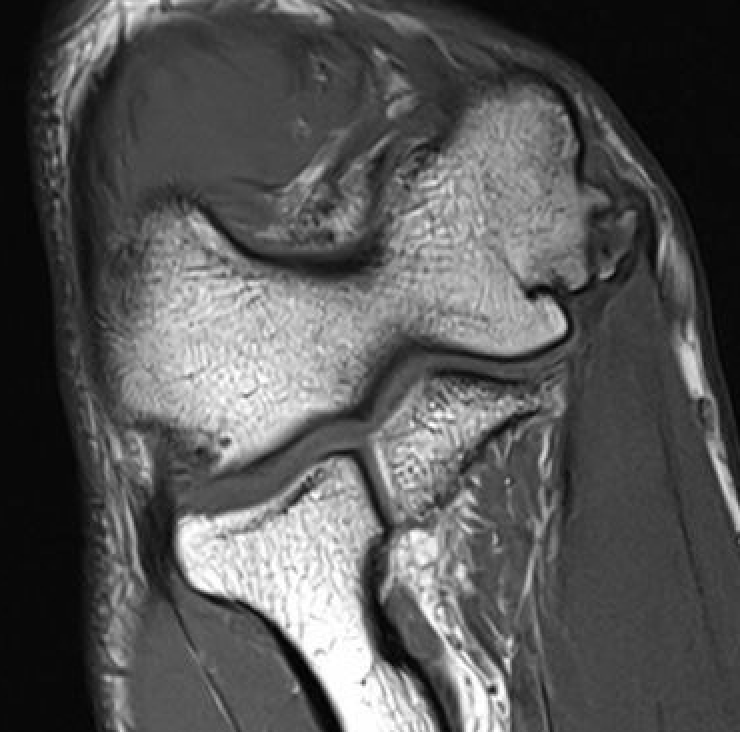

Modified Jobe / Figure 8 reconstruction

MCLMCL

Technique

Proximal insertion - Y shaped tunnel in medial epicondyle

Distal insertion - transverse tunnel across ulna / sublime tubercle

Docking technique

Docking UCL

Proximal insertion - blind tunnel in medial epicondyle